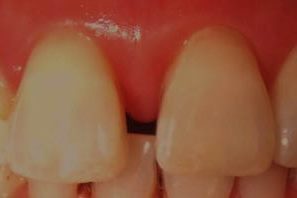

顕微鏡下で歯ぐきの外科処置を行い歯ぐきの治癒を妨げないよう髪の毛より細い縫合糸(7-0ナイロン)にて縫合した後の写真です。肉眼では取扱いの困難なほど細い糸なので歯ぐきも綺麗に治癒してきます。

| 施術の説明 | 顕微鏡を用いた歯ぐきの外科処置になります。歯ぐきの下の感染物質をきれいにしたあとに7−0ナイロン糸という極細の縫合糸を用いて歯ぐきの縫合をしています。 |

| 施術のリスク、副作用等 | 歯周外科処置のリスクは通常術後の歯ぐきの腫れ、出血、疼痛等を多少なりとも伴う処置になりますので抗生物質と鎮痛剤の服用を今回は1日しております。ただし顕微鏡下の処置によりそれらを最小限に抑えるように低侵襲で行っております。 |

| 施術の価格 | 55,000円 |